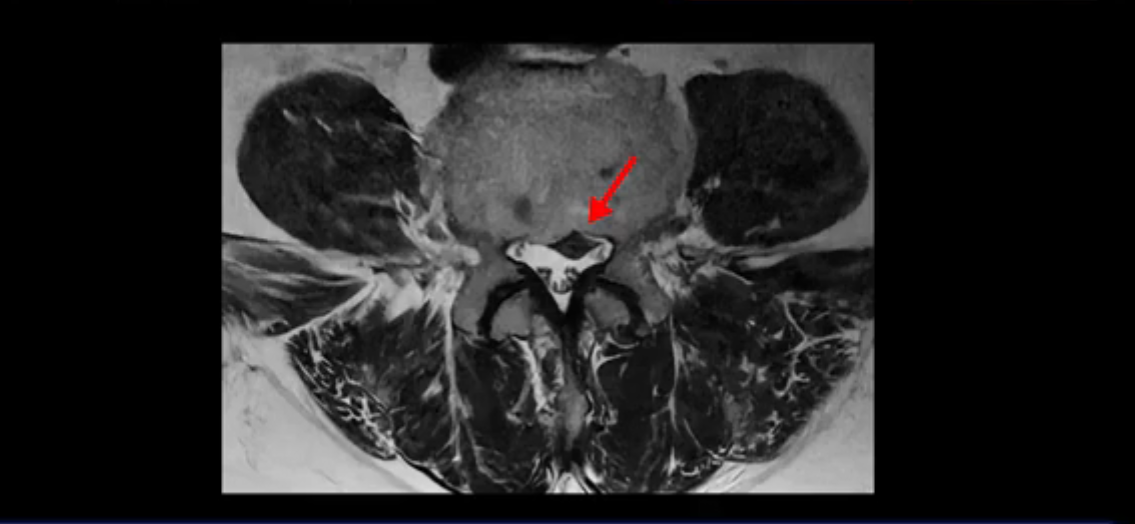

보시다시피 흘러 내려온 디스크 수핵이 신경 공간의 왼쪽으로 보입니다.

그런데 이분은 4번 5번에도 디스크 파열이 있습니다.

가운데로 심하게 밀려 나와 있는데요.

또 4번 5번에는 협착으로 척추관이 많이 좁아져 있습니다.

또 왼쪽 신경 가지들이 빠져 나가는 신경구멍들이 여러 마디가 좁아져 있습니다.

이런 이유들 때문에 왼쪽 엉덩이부터 종아리, 발가락까지 저리고 아픈 겁니다. 그래서 서둘러 병원에 가셨는데요. 그래서 서둘러 병원에 가셨는데요. 여러분이 꼭 아셔야 할 게 이렇게 다리가 심하게 저리고 아프면 X-ray만 찍을 게 아니고 MRI를 찍어 보시는 게 맞습니다. X-ray로는 디스크가 터졌는지 신경구멍이 좁아진 협착이 있는지를 정확히 할 수가 없습니다. 그래서 이분은 당장 아픈데 해결이 안 되니까 제주도에서 유명하다는 한의원으로 갔습니다.